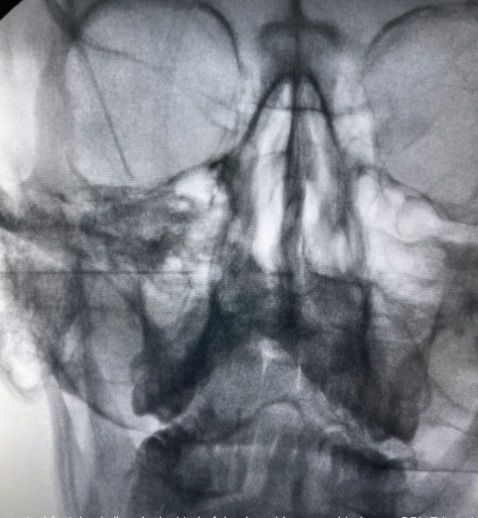

- Ξυλοκαΐνη ενδορινικά με στυλεό για τον αποκλεισμό του σφηνοϋπερώιου γαγγλίου

- Block του σφηνουπερώιου γαγγλίου με τοπικό αναισθητικό και κορτιζόνη

- Νευρόλυση του σφηνουπερώιου γαγγλίου με χρήση ραδιοσυχνοτήτων